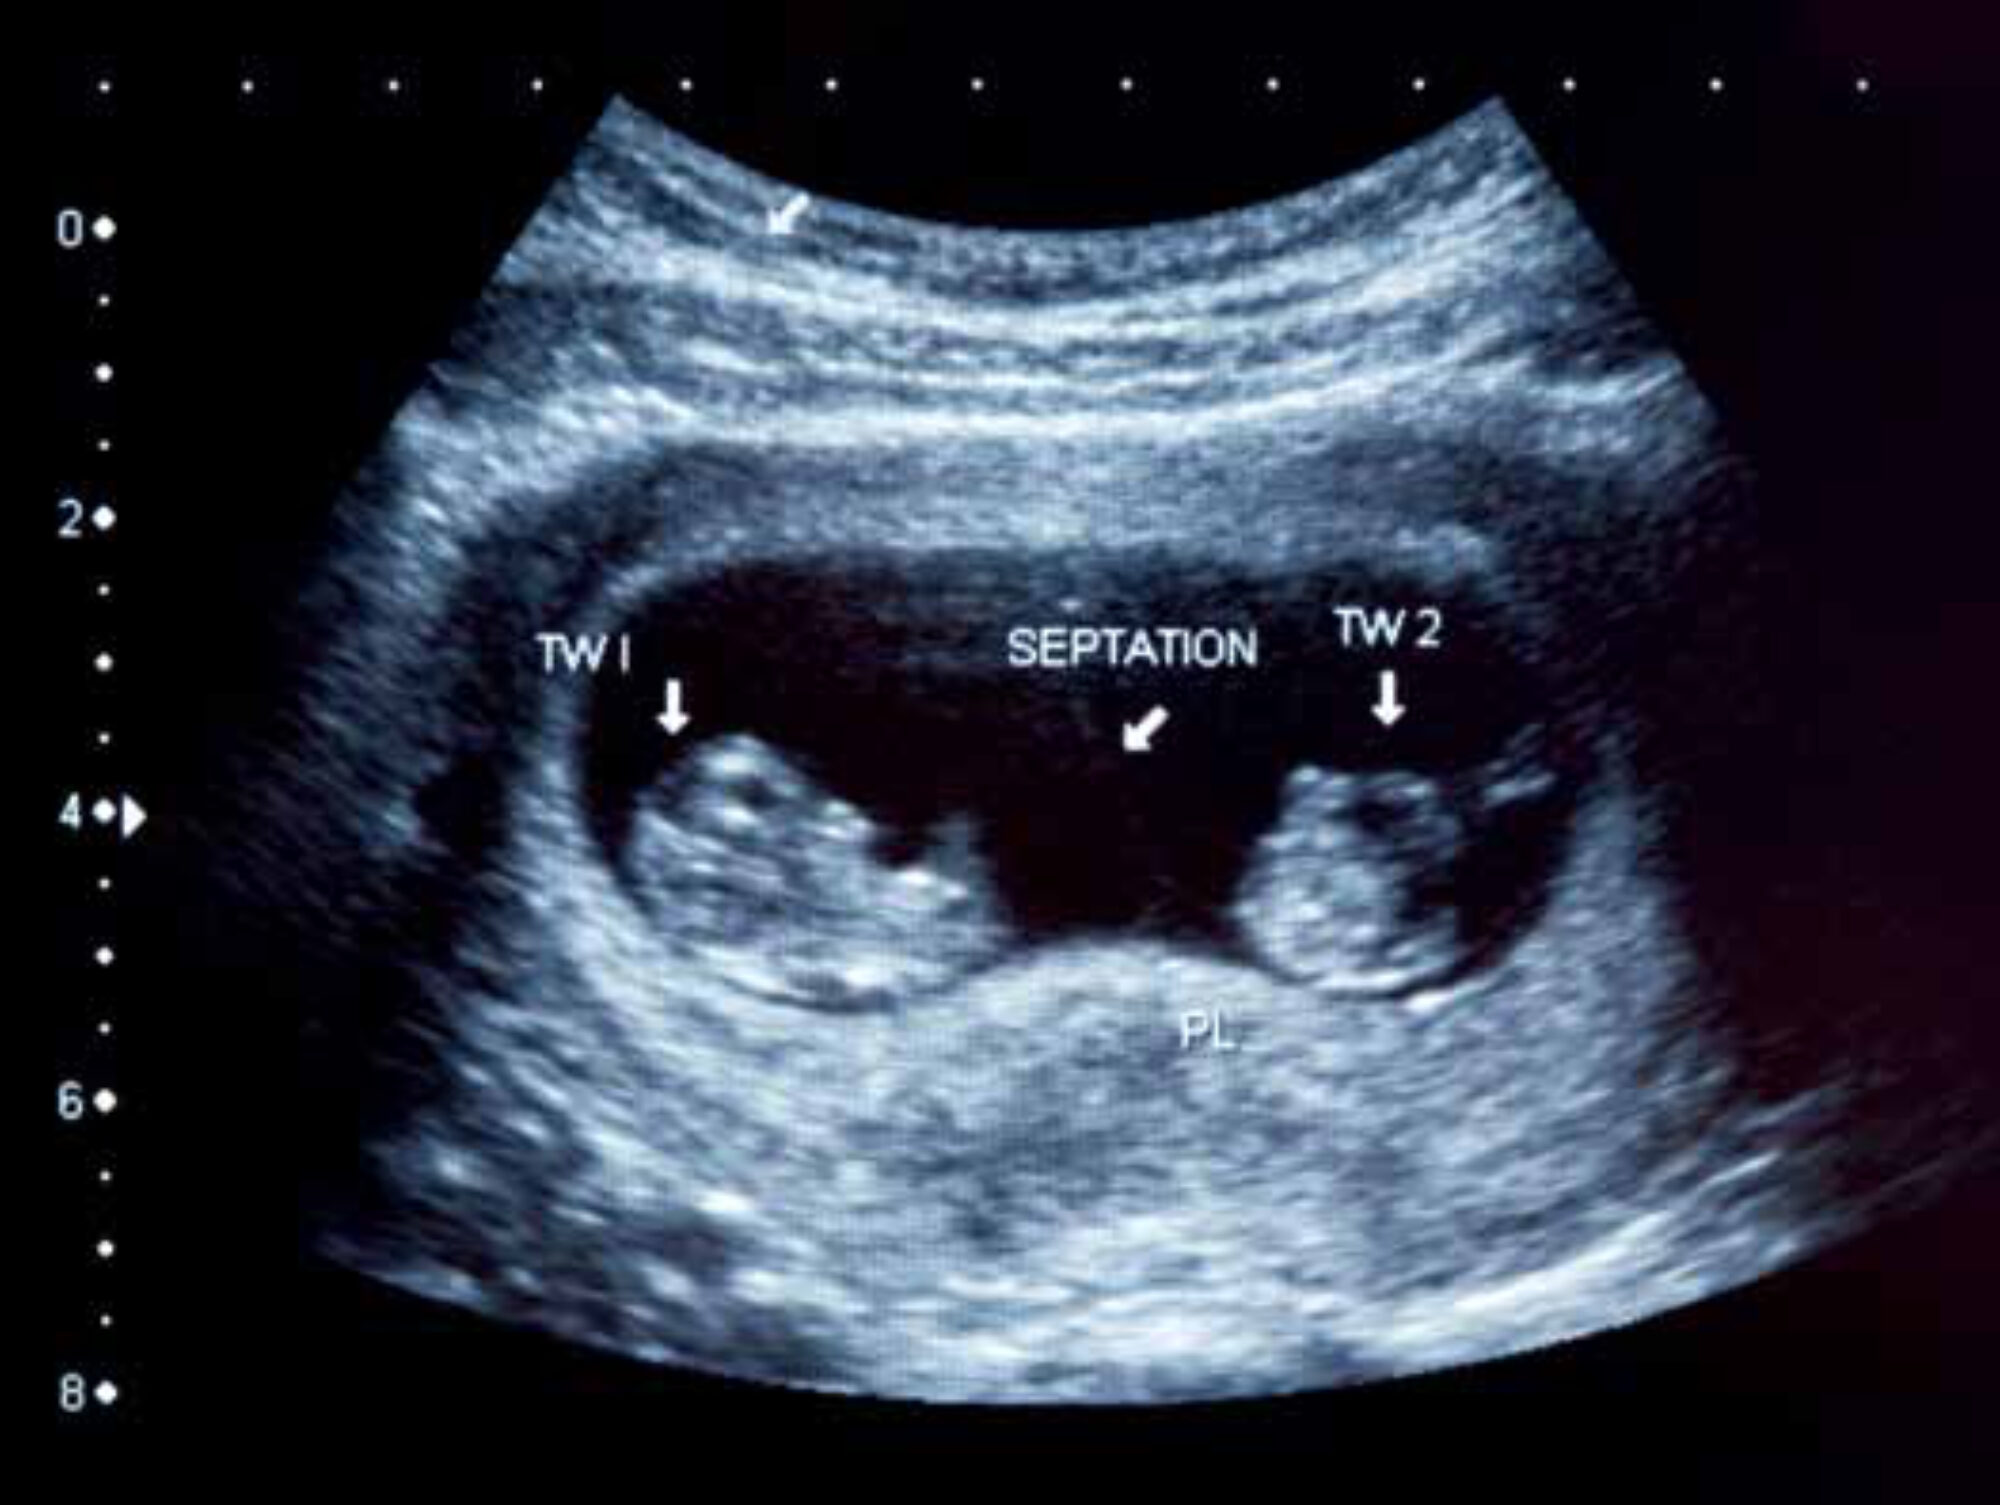

Deep learning is a machine learning technique that can be used to develop computer algorithms that can automatically perform tasks. This technique has become popular in recent years and is already used for various applications like speech recognition, natural language processing, and facial recognition. Since 2013, deep learning has also been successfully applied in the field of medical imaging.[5] We combined deep learning algorithms with the OSP in order to eliminate the need for a trained sonographer to interpret the ultrasound images. A large dataset was required for the development of these algorithms. The OSP was therefore performed on more than 300 pregnant women at St. Luke’s Catholic Hospital. This data was then used to develop the deep learning algorithms. The developed algorithms were used for three different applications: determining foetal presentation, detecting twin pregnancies, and determining gestational age by estimating the foetal head circumference.[6]